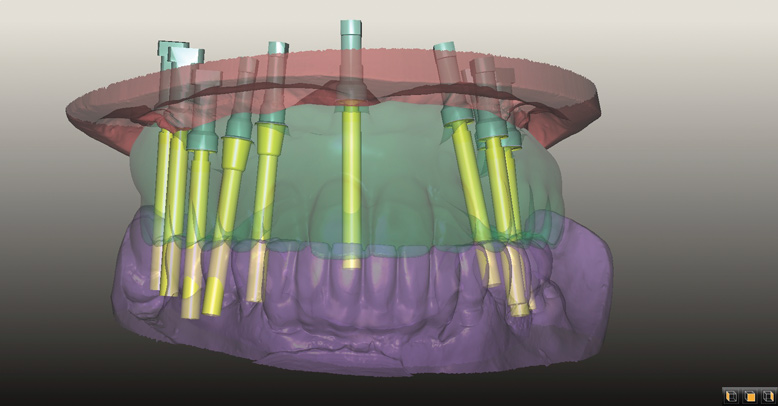

Fig 9. CT guided surgery planning. Ten implants were planned, including a maxillary anterior implant to be placed in the anterior nasal spine.

Figure 9